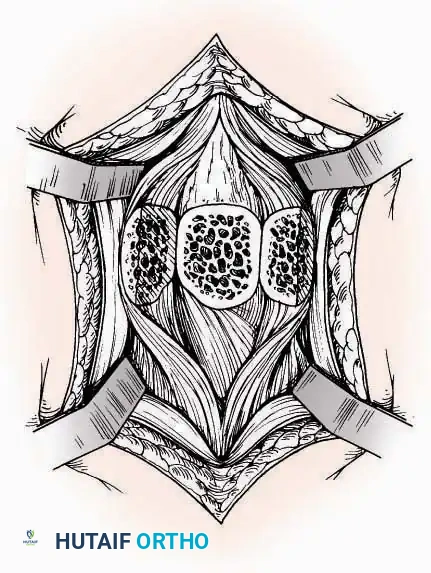

Approaches to the Metatarsophalangeal Joints of the Lesser Toes

Indications: Metatarsal head resections (Weil osteotomies), plantar plate repairs, or correction of severe crossover toe deformities.

Surgical Technique:

* Incision (2nd, 3rd, 4th Toes): Utilize a dorsolateral longitudinal incision parallel to the corresponding extensor tendon. This avoids the primary dorsal cutaneous nerves which typically run strictly dorsally.

* Incision (5th Toe): Best exposed via a straight or gently curved dorsal or dorsolateral incision to avoid the lateral shoe-wear friction zone.

* Capsulotomy: The joint capsules are opened longitudinally. For adjacent MTP pathology (e.g., 2nd and 3rd MTP joints), a single dorsal incision placed in the intermetatarsal space can be utilized to access both joints via medial and lateral subfascial windows.